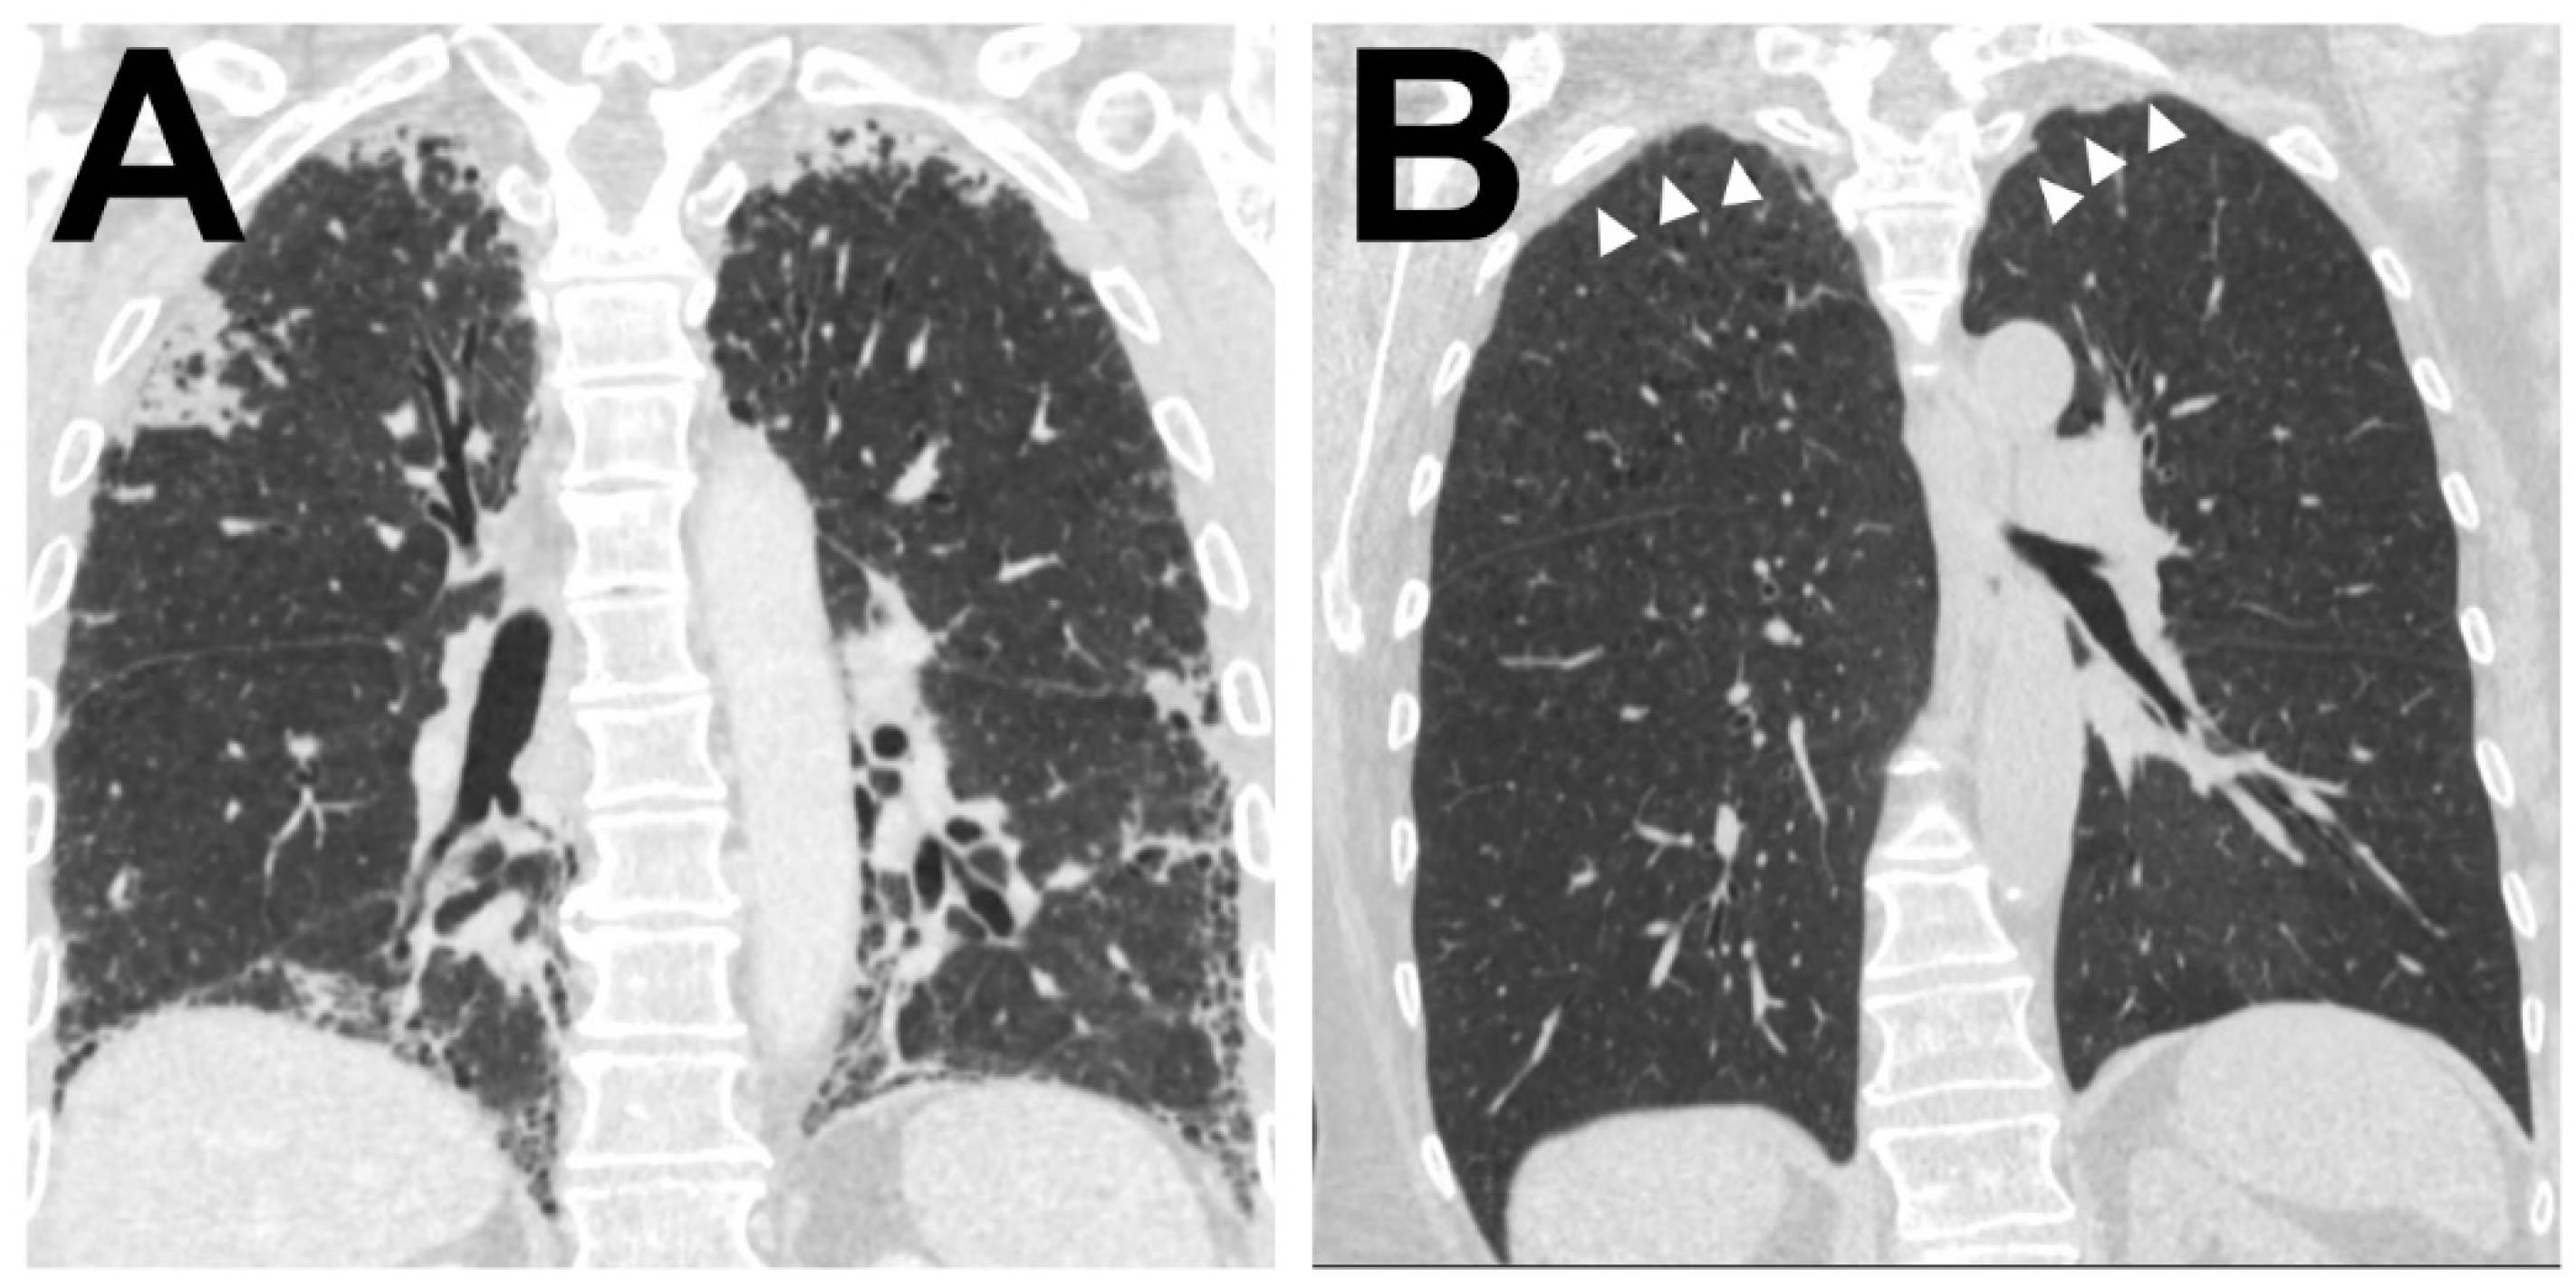

Further radiological information was available in 38 (84%) patients. Of these 38 CT scans, 26 (68%) confirmed a main pattern of alveolar fibro-elastosis, in 10 (26%) patients this was a minor pattern and in 2 (5%) remaining patients, there was no radiologic evidence for AFE (see Figure 4 for representative images)

Figure 4. Radiological correlate of AFE Illustration of the two typical radiological patterns accompanying a histologic AFE diagnosis. (A). Radiological PPFE pattern with typical (sub)pleural distribution of fibrosis. (B) Apical cap.